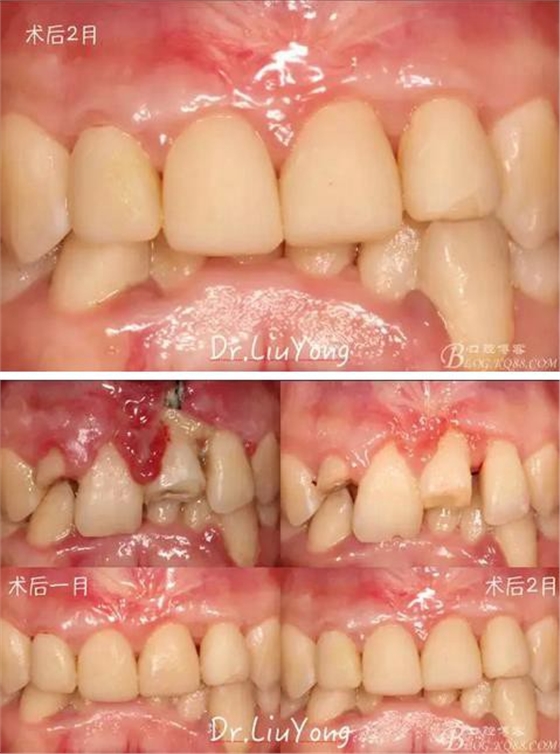

膜齦手術(shù)后2月復(fù)查,可以明顯觀察到,B12之間的牙齦乳頭明顯高度增加,黑三角得到很大改善,如下圖:

最終A2-B2全瓷修復(fù)體戴入口內(nèi),如下圖:

術(shù)前到最終修復(fù)歷時半年余,如下圖: